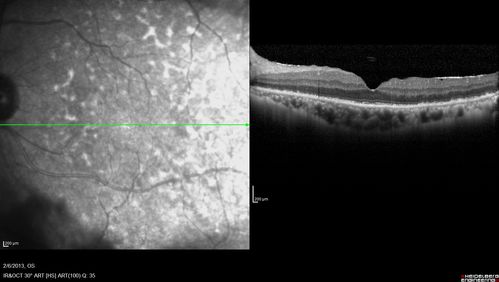

Vasculitis - Retinitis - Uveitis - Vision NLP right eye , 20/50 left eye

Unknown - Possible Syphilitic